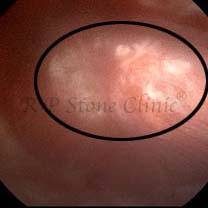

Kidney stone is a solid mass of CRYSTALS. It is the process of crystallization which initiates the formation of kidney stones. This happens in nephrons or units of kidney. Once a small crystal is formed, it can both grow & unite with other crystals leading to the formation of small concretion which eventually forms a stone. Once these large crystals detach from the collecting ducts, the process of stone formation starts in the renal collecting system. A recurrent kidney stone former is advised to know a little bit about something known as Randall’s plaque. Alexander Randall discovered plaques on the renal papillae eight decades back based on examination of 1154 pairs of autopsied Kidneys. He described these renal papillary lesions as cream colored or milk patch areas composed of calcium phosphate & calcium carbonate. These plaques could act as NIDUS for formation of KIDNEY STONE. Calcium Oxalate stone can form on this nidus & then detaches from this plaque to become a free floating stone in the collecting system of kidney

These images are taken as snap shots from the video recording of RIRS Surgery done at our hospital. These are Randall’s Plaques seen with Digital FLEX XC & Digital FLEX XC S. The cream or whitish patches are seen on the tips of RENAL PAPILLAE as seen in images below.

Randall’s Plaques may lead to the formation of Stones.

Those kidney stone patients who have Randall’s Plaques in their kidneys are more likely to form stones again (Recurrent Stones).